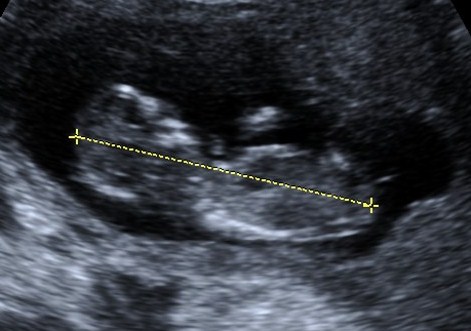

This is from my 13 week scan. I am unsure if the pictures are clear enough to take a guess at gender.

Looking forward to your guesses!

It's really hard, but my immediate thought was boy. It's slightly angled and there seems to be a line on top... If that makes sense. The bottom pic I think I see a shadow above the nub?

So yeah with it being relatively unclear it's hard to tell but I'd lean boy, just.

If that's a nub in the bottom pic I'd guess boy I think. They are a little blurry so it's hard. I think it could go either way though!

Yes I think so too if that's the nub it does seem to be angled upwards. I'm guessing boy.

Hard to say, but I definitely see an upward angle. I have to guess boy.

slightly leaning boy

at 13 weeks I would hope to see a little more going on for a boy BUT I don't feel like those pics are clear at all and I am 50-50